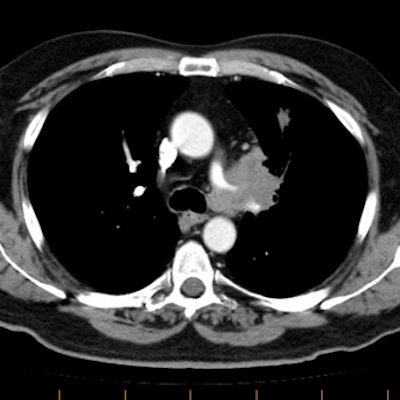

Example 1: This is a case of squamous cell carcinoma that was found to be invading the chest wall at surgery. CT findings which suggested the diagnosis of chest wall invasion in the case include focal pleural thickening below the mass, more than 3 cm of contact between the mass and the pleural surface, an obtuse angle between the mass and the pleural surface, and encroachment on or increased density in the underlying extra-pleural fat.